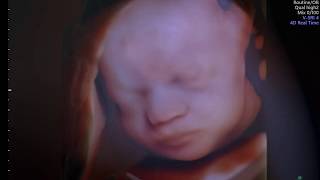

1:30 Fetal Vision Imaging 3D ultrasound Baby Of The Month September 2010 Fetal Vision 176 views - 15 years ago

1:43 Fetal Vision Imaging 3D Ultrasound Baby of the Month ~ August 2010 Fetal Vision 552 views - 15 years ago

3:02 Fetal Vision Imaging 2010 "The Ultimate 3D/4D Experience" Fetal Vision 7.6K views - 15 years ago

2:25 Fetal Vision Imaging 4D Ultrasound www.fetalvisionimaging.com Fetal Vision 48.7K views - 18 years ago